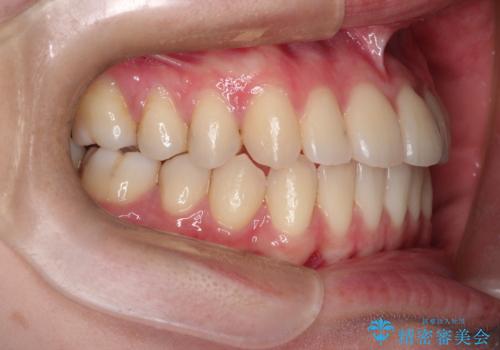

インビザラインによる非抜歯矯正 ガタガタな歯並びを整った歯並びへ

- 前歯のガタガタを主訴に来院されました。

抜歯矯正も考えられる状態でしたが、非抜歯矯正を希望されました。

使用時間を守っていただけたので、スムーズに治療を終わることができました。